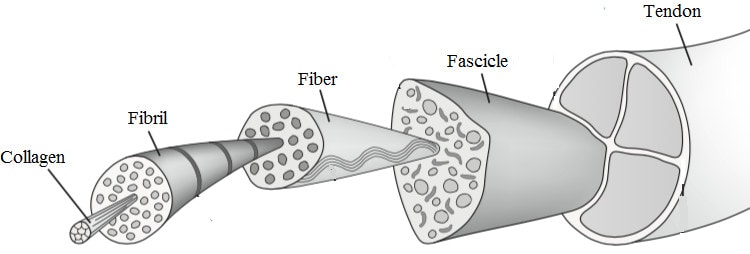

2. Не сме в състояние да възстановим/излекуваме дегенеративната патология на сухожилията. С други думи, никаква операция, никаква терапия с ударни вълни, никакви инжекции и дори упражнения не са в състояние да възстановят или излекуват дегенерирало сухожилие. Докинг и др. (2019) смятат, че при слаба способност да усещат натоварване на опън клетките в дегенеративната част на сухожилието могат да бъдат недостатъчно стимулирани и да не получават необходимите механични стимули за ремоделиране, което обяснява ограничената способност на патологичното сухожилие да се ремоделира и нормализира. Макар да си мислите, че това може да е лоша новина, добрата новина е, че не е и необходимо. Проучване на Tsehaie и др. (2017) показва, че 24-седмичните ексцентрични упражнения за ахилесовото сухожилие не водят до промени извън границите на откриваемото изменение в сухожилието, но въпреки това пациентите се подобряват. Те също така установиха, че параметърът на МРТ в началото на изследването предсказва промяната в симптомите, така че дори ако МРТ изглежда ужасно, това няма значение.

5. Интензивното натоварване на сухожилията води до нетна деградация на колагена за период до 36 часа. Проучване на Magnussen et al.(2010) показва този ефект при три групи много интензивни упражнения, които са 36 км бягане, 1 час повтарящо се ритане и 10 серии от 10 повторения на колянно разгъване при 70% максимална доброволна контракция. Това означава, че се нуждаем от достатъчно време за възстановяване, за да предотвратим тендинопатията, и че е препоръчително тренировките за сухожилията да се провеждат на всеки втори ден или по-рядко.

6. Патологичното сухожилие има по-добра структура от нормалното сухожилие(Docking et al. 2015). Това означава, че можем да натоварим тези сухожилия, защото разполагаме с много добра тъкан. Не са необходими никакви терапии за патологията на сухожилията, тъй като така или иначе не можем да променим структурата на патологичната част. Поради тази причина Докинг и колегите му измислят цитата "Лекувайте поничката, а не дупката" - с други думи, съсредоточете се върху здравата структура, а не върху патологичната част.

Патологичното сухожилие има по-добра структура от нормалното сухожилие (Docking et al. 2015)